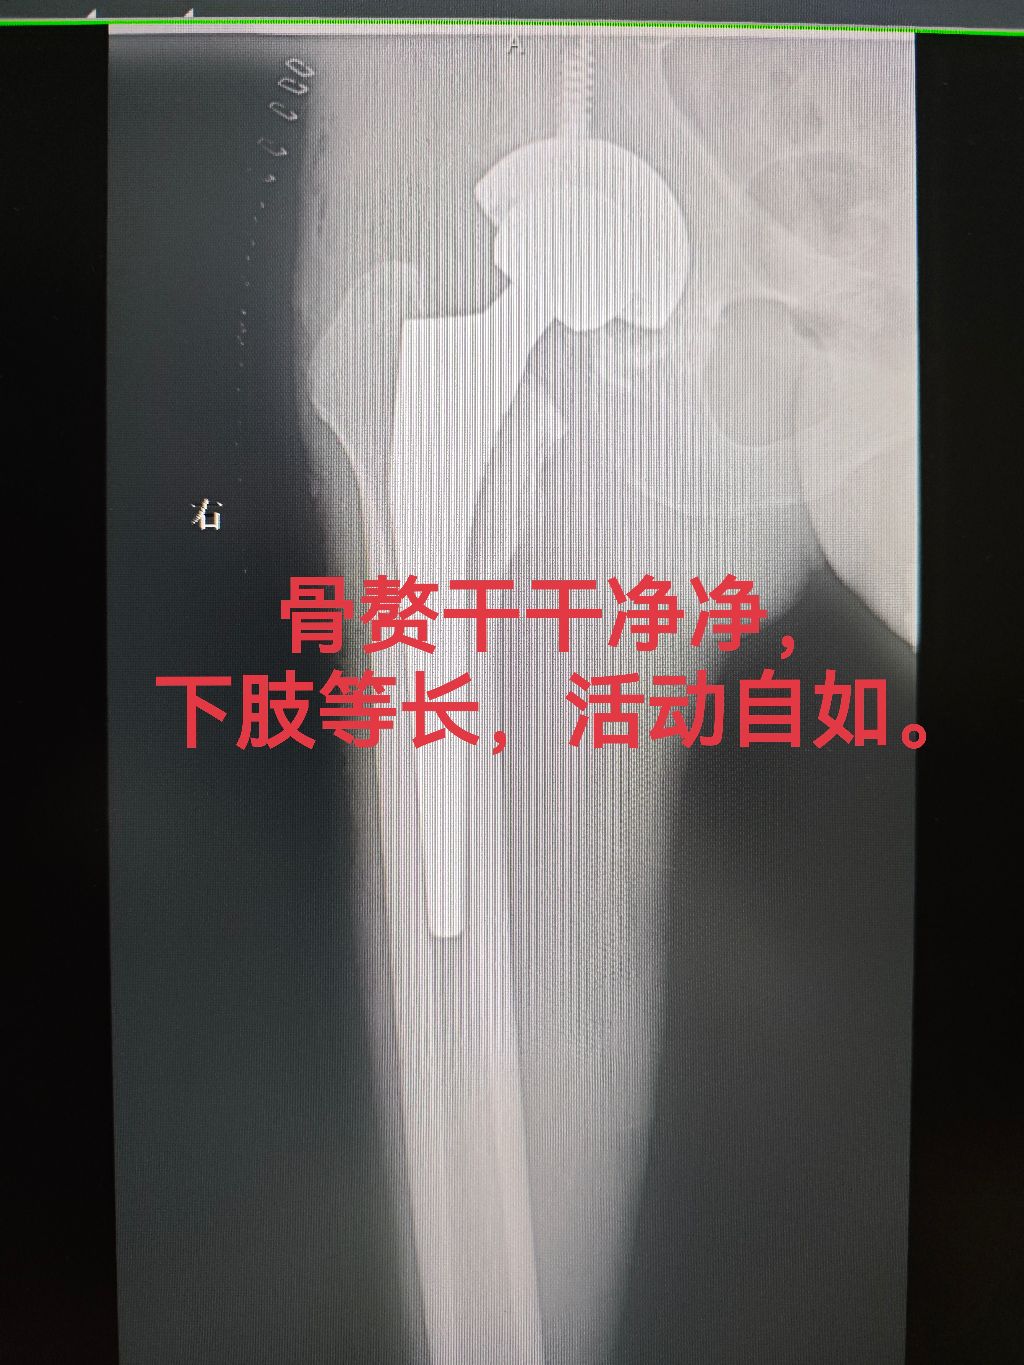

股骨头坏死。股骨头坏死合并骨关节炎15年,缩短3cm,大量骨赘形成,活动度极差。不清除骨赘,活动度受影响,清除骨赘,手术难度和风险增加。尽力而为,不留遗憾。对医生来说,只是一台手术,对患者而言,是一生的托付!医生,一生,对患者常怀怜悯之心,对手术常怀敬畏之心。 股骨头坏死髋关节置换